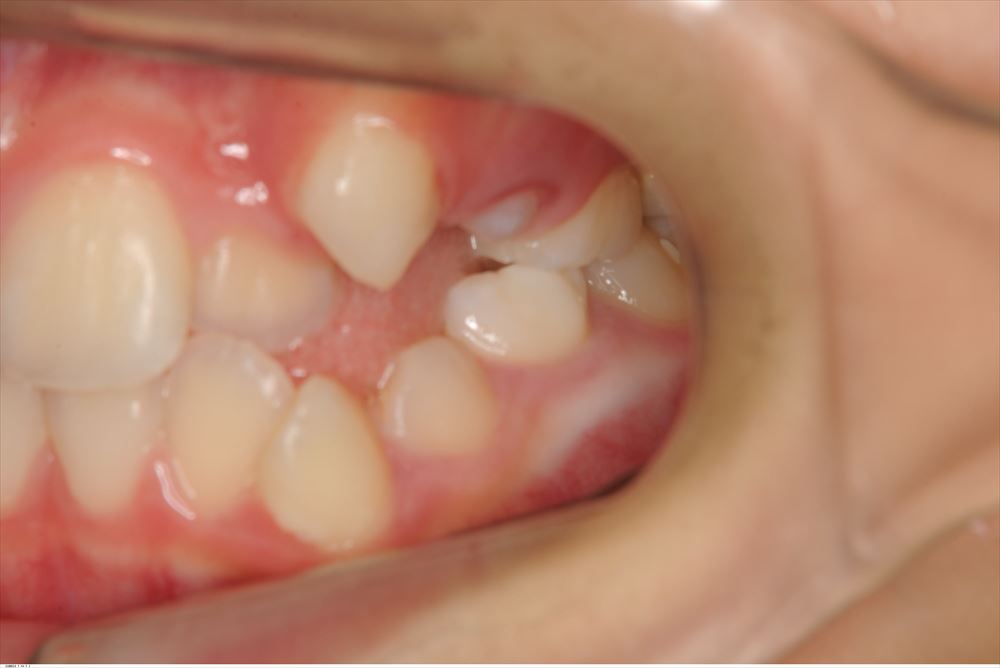

今日は矯正の装置を外した女の子。外してとても喜んで頂けました。

術前。あらま。